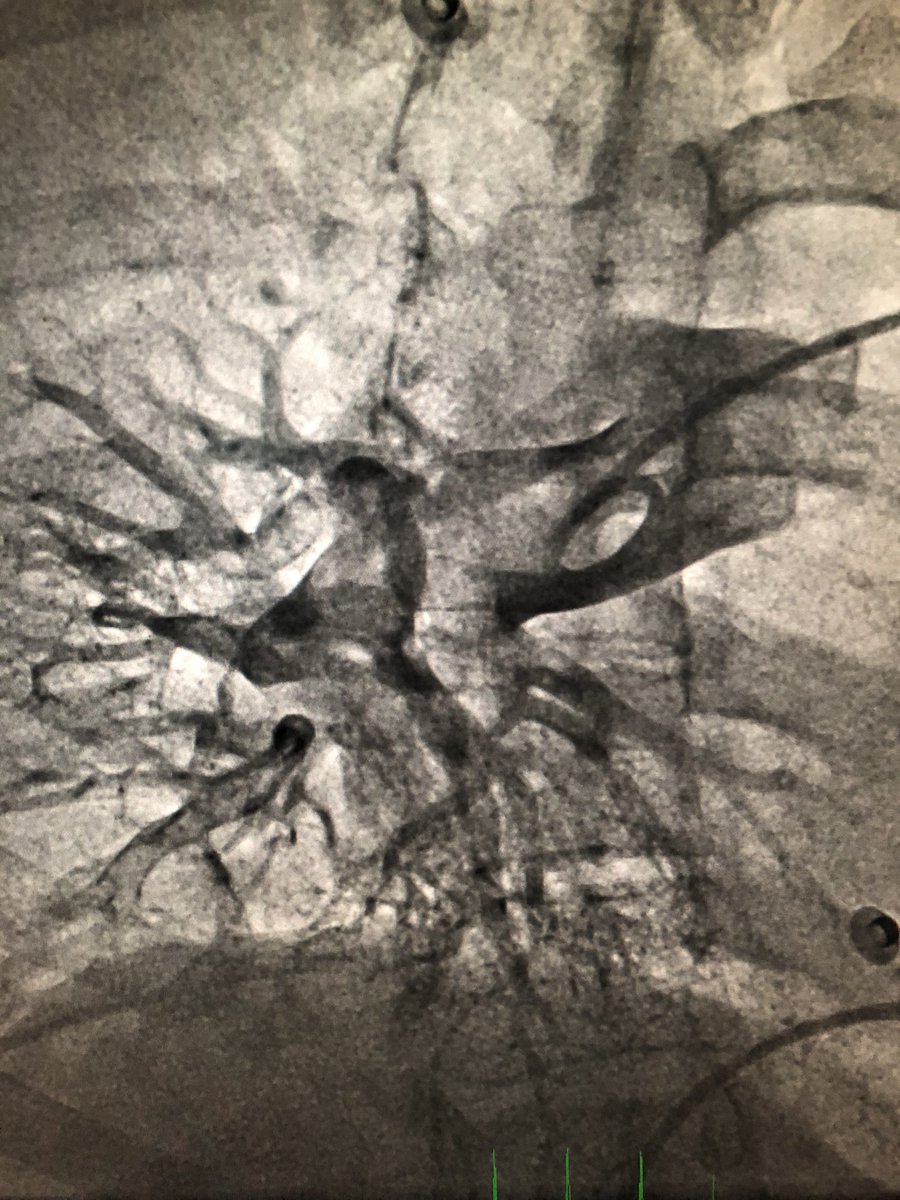

First case in @Cardio_H12O with #flowtriever (@InariMedical) in a 80YO👴 with high-risk #PE and syncope (head trauma). Uneventful 24h stay in ICU. Large thrombus aspiration by @TrevillaAgustin and @frenandosarnago. @pabl0salinas

4

13

59